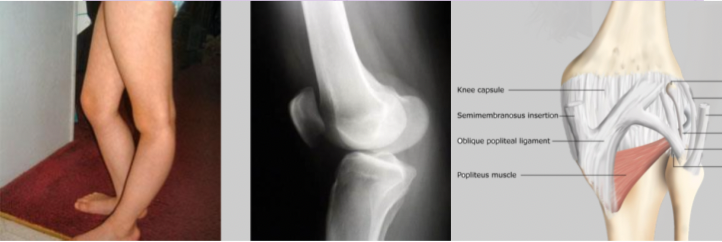

Genou recurvatum

- déf

- cause

Hyperextension genou

Causé par l’hyper-laxité des liga du genou